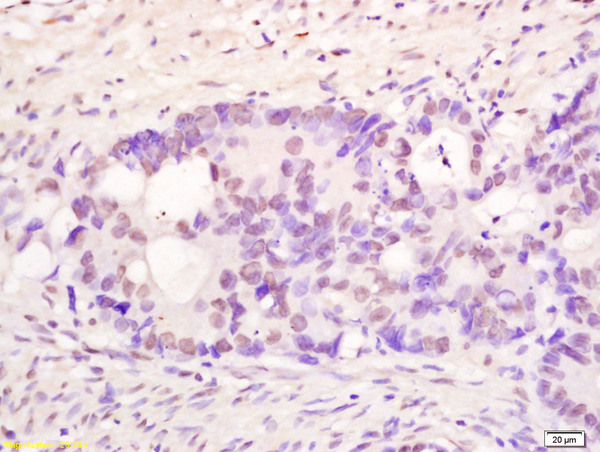

IHC-P analysis of human colon carcinoma tissue using GTX60281 PMS1 antibody.

Dilution : 1:200